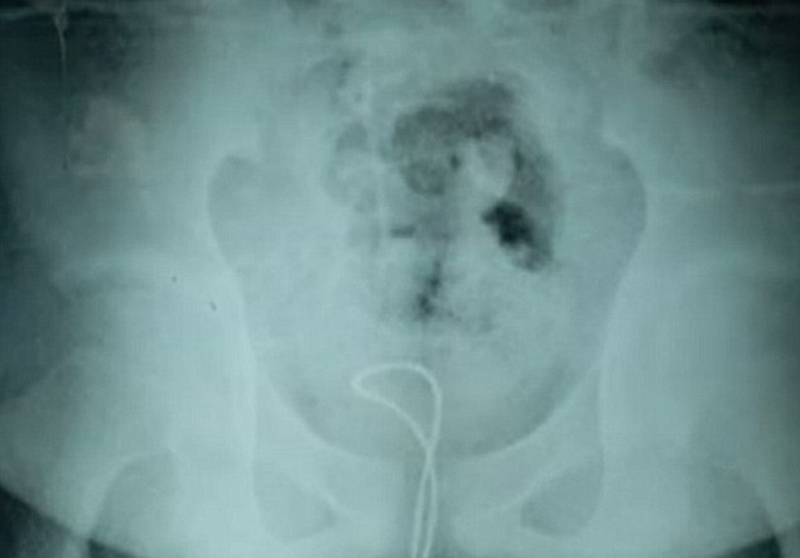

Il dottor Xu Liyan del reparto di urologia ha spiegato che il cavo si è attorcigliato ed è rimasto incastrato nel pene di Duoduo raggiungendo la vescica del ragazzo. “Si vede bene dalla raggi x – ha spiegato il medico – ed è questo il motivo per cui il ragazzo non riusciva a togliere il cavo dal pene. Sapete quanto era lungo il cavo nel pene di Duoduo? 10 centimetri! Ma il ragazzo era curioso di sapere che sensazione si provasse… Aveva sentito i suoi compagni di scuola che giocavano con il loro pene e aveva deciso di fare come loro”.